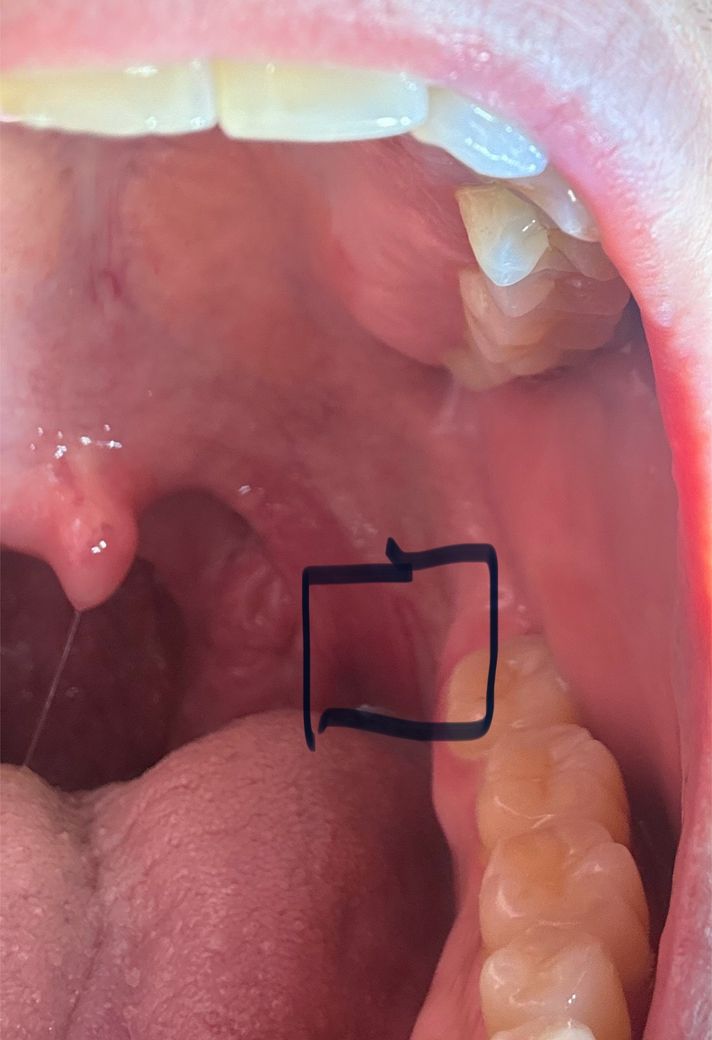

입안 턱근육 긴장과 상처 문의드립니다.

최근 턱근육이 긴장된고 뻐근한 같은느낌인데 입안을 보니 턱쪽 이상한 상처같은게 있습니다. 문제가 무엇인가요? 그리고 약은 무슨약을 먹어야하나나요?

• 1번 째 사진

턱근육 증상과는 별개의 상처같습니다 어떤 자극으로 인해 궤양성 병소가 생긴것으로 의심됩니다 구강내과가서 약 처방 받으세요

• 안녕하세요. 김지훈 치과의사입니다. 턱근육의 긴장과 해당 부위는 상관이 없으며 사진상으로는 특별히 문제점이 보이지는 않습니다.

턱근육의 긴장과는 연관성이 없는 부위입니다. 아마 음식등을 드실때 저부위에 자극이 가서 그러는거 같습니다.